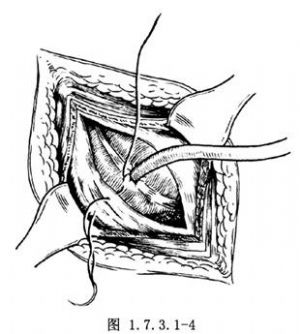

4.结扎第2荷包缝合线,使盲肠壁内翻。再将线尾穿过腹膜后打结,使盲肠壁固定于腹膜上。造口管从腹壁切口或右下腹另一戳口引出(图1.7.3.1-4)。